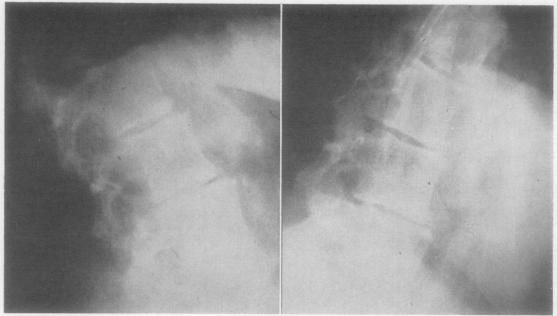

RHEUMATOID ARTHRITIS OF THE LUMBAR SPINE.

Ann Rheum Dis. 1964 May;23(3):205-17. doi: 10.1136/ard.23.3.205.